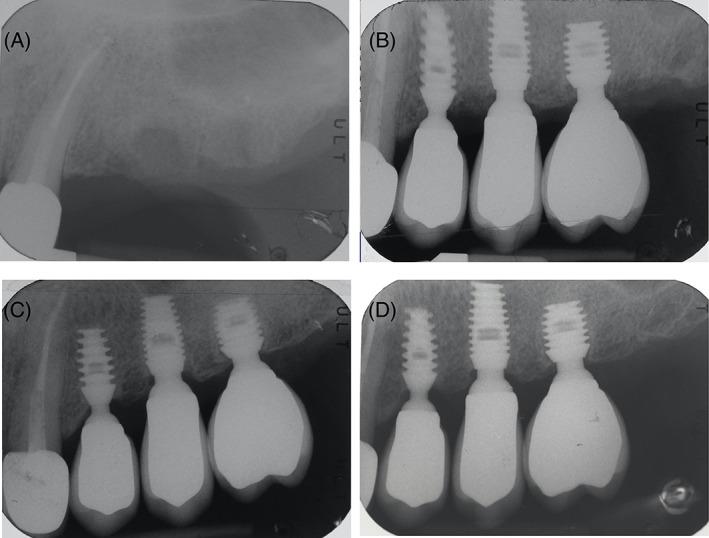

The aim of this retrospective study was to evaluate implant survival, marginal bone loss, and peri-implant complications in 333 locking-taper short and ultra-short implants.

Implants were placed in the maxillary and mandibular posterior regions of 142 patients. Clinical and radiographic examinations were performed at 5-year recall appointments.

All implants placed consisted of 8.0-, 6.0-, and 5.0-mm length, 38.14%, 34.53%, and 27.33%, respectively. Three hundred thirty-two implants (one early failure) were rehabilitated with single crowns in 141 patients. In 45.48% of the implants the crown-to-implant ratio was ≥2, with a mean value of 1.94. Overall implant-based survival after 5 years of follow-up was 96.10%: 96.85%, 95.65%, and 95.60% for 8.0-, 6.0-, and 5.0-mm length implants, respectively (p = 0.82). Overall patient-based survival was 91.55%. Regarding crestal bone level variations, average crestal bone loss and apical shift of the "first bone-to-implant contact point" position were 0.69 and 0.01 mm, respectively. Setting the threshold for excessive bone loss at 1 mm, during the time interval from loading to follow-up, 28 implants experienced loss of supporting bone greater than 1 mm: 19 of them (67.85%) were surgically treated with a codified surgical regenerative protocol. After 60 months, a peri-implantitis prevalence of 5.94% was reported, with an overall implant success of 94.06%: 95.93%, 92.73%, and 93.10% for 8.0-, 6.0-, and 5.0-mm length implants, respectively (p = 0.55).

本回顾性研究旨在评估 333 个锁定锥形短种植体和超短种植体的种植体存活率、边缘骨丧失和种植体周围并发症。

将种植体放置在 142 名患者的上颌和下颌后牙区。在 5 年的随访中进行临床和影像学检查。

所有植入物的长度分别为 8.0mm、6.0mm 和 5.0mm,分别占 38.14%、34.53%和 27.33%。141 名患者的 332 个种植体(1 个早期失败)采用单冠修复。在 45.48%的种植体中,冠-种植体比≥2,平均值为 1.94。5 年随访后,种植体总存活率为 96.10%:8.0mm、6.0mm 和 5.0mm 长度的种植体分别为 96.85%、95.65%和 95.60%(p=0.82)。种植体总存活率为 91.55%。关于牙槽骨水平的变化,平均牙槽骨丧失和“第一个骨-种植体接触点”位置的根尖移位分别为 0.69mm 和 0.01mm。在从加载到随访的时间间隔内,将骨量过度丧失的阈值设定为 1mm,28 个种植体经历了大于 1mm 的支持骨丧失:其中 19 个(67.85%)采用编码的外科再生方案进行了手术治疗。60 个月后,报告了 5.94%的种植体周围炎患病率,总体种植体成功率为 94.06%:8.0mm、6.0mm 和 5.0mm 长度的种植体分别为 95.93%、92.73%和 93.10%(p=0.55)。